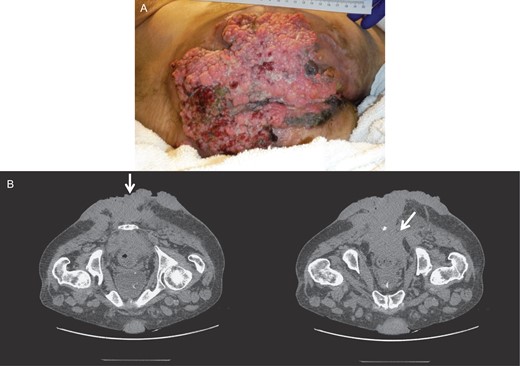

Four months later, after completion of the chemoradiotherapy, there was a significant resolution of the tumor (Fig. 3). No lesions could be felt on the rectal exam. The endoscopy and CT scan after another three months confirmed regression without presence of lesions. The scarred and necrotic soft tissue appeared to be residual from the chemoradiation and was debrided.

Gross image (A) and CT of the pelvis and perineum (B) showing tumor resolution and residual lesions after chemoradiation therapy.